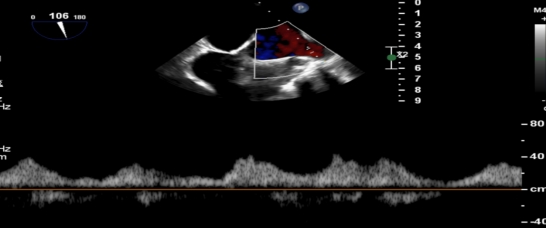

术后PV前向改善

术后第二天,患者顺利返回普通病房,并可自主下床活动,进食、睡眠等生活状态逐步恢复正常。术后超声显示残余轻度反流,肺静脉血流恢复正常,患者症状较前明显改善,活动耐量提升,生活质量显著提高。术后1周,患者各项生命体征平稳,顺利康复出院。“没想到不用开胸就解决了这个大毛病,还能恢复这么快、这么好!”出院当天,患者及家属对手术效果和就医体验给予高度评价,并衷心感谢医护人员的专业诊疗和无微不至的关怀照护。